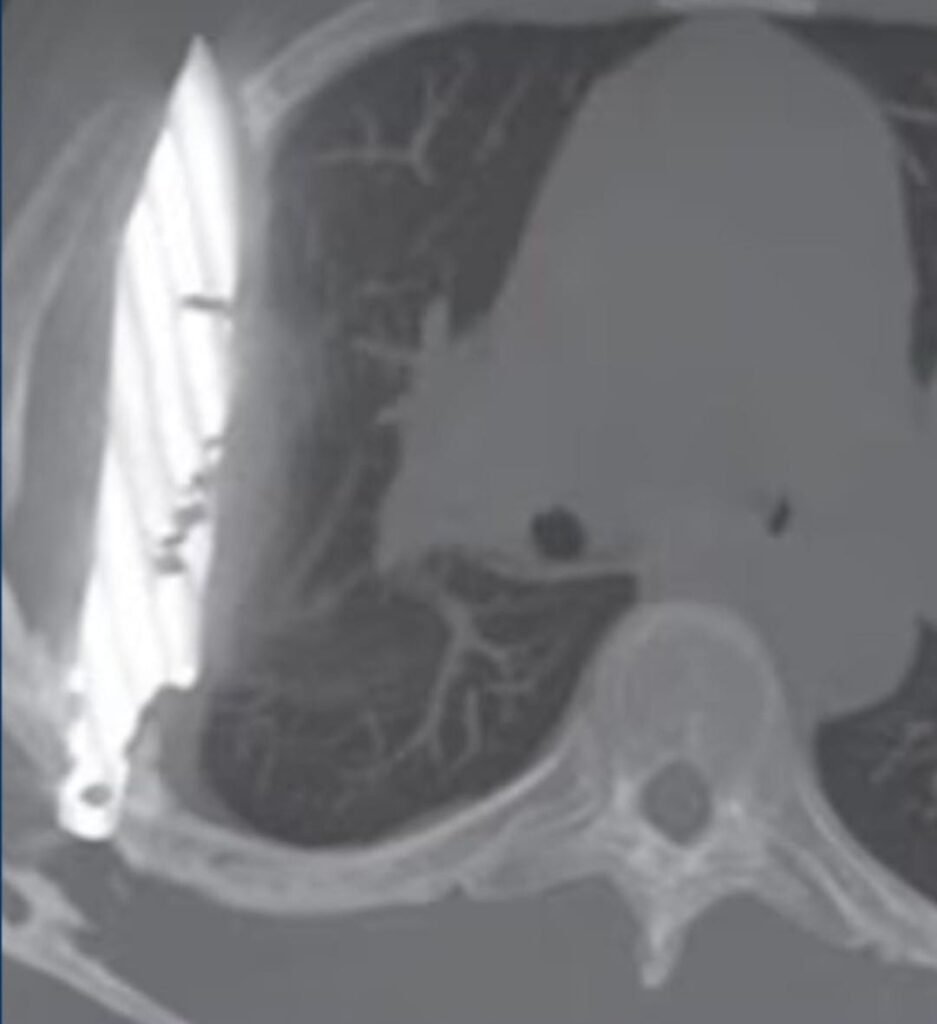

El paciente, que permaneció anónimo, buscó atención médica tras notar una secreción de pus en su pezón derecho. Los médicos quedaron perplejos al descubrir, a través de estudios de imagen, que un objeto extraño se había alojado en su tórax. La revelación no solo fue inesperada para el equipo médico, sino también para el propio paciente, que relató haber llevado una vida completamente normal, libre de dolor, tos o dificultades respiratorias, durante los ocho años que el cuchillo permaneció en su cuerpo.

Según el informe médico, la pieza clave del rompecabezas fue un violento ataque que el hombre sufrió hace ocho años. En aquel entonces, las limitaciones en los recursos sanitarios de su localidad impidieron un diagnóstico completo. Aunque las heridas externas fueron tratadas y suturadas, la falta de radiografías o ultrasonidos hizo que el cuchillo pasara desapercibido, quedando silenciosamente alojado en su cuerpo mientras el hombre seguía con su vida.

El equipo médico procedió a la extracción exitosa del objeto, poniendo fin a una increíble historia de supervivencia. Este caso subraya los desafíos de la atención médica en regiones con recursos limitados, donde las heridas graves a menudo no son examinadas en profundidad, y resalta la asombrosa capacidad de adaptación del cuerpo humano a circunstancias extremas.